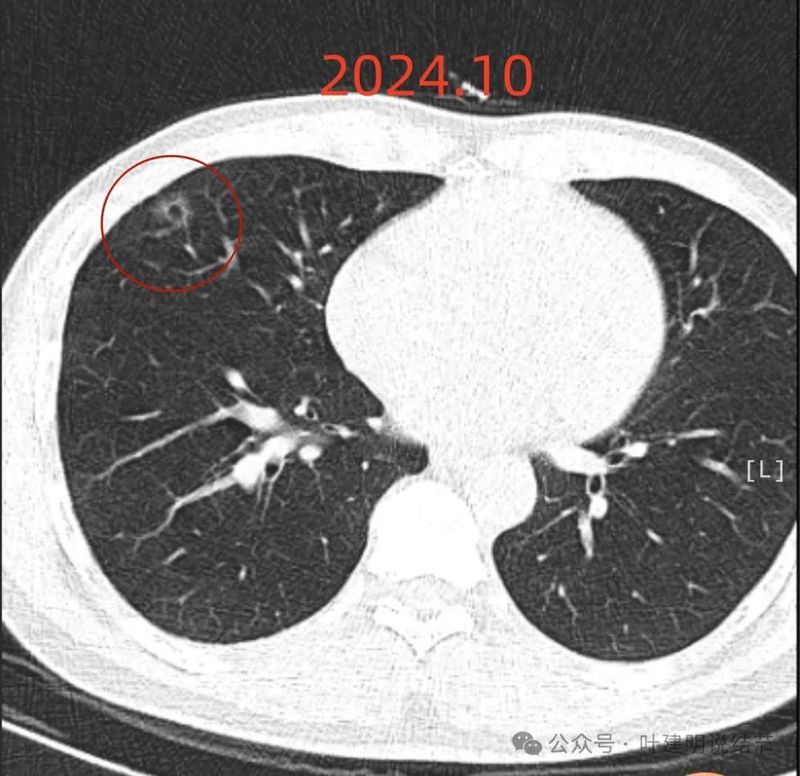

上图是2024年10月的,可惜不是薄层影像,与2023年的可比性差。